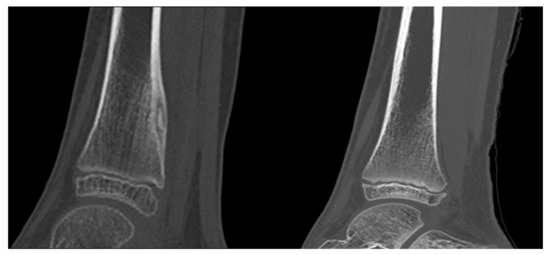

3. Results